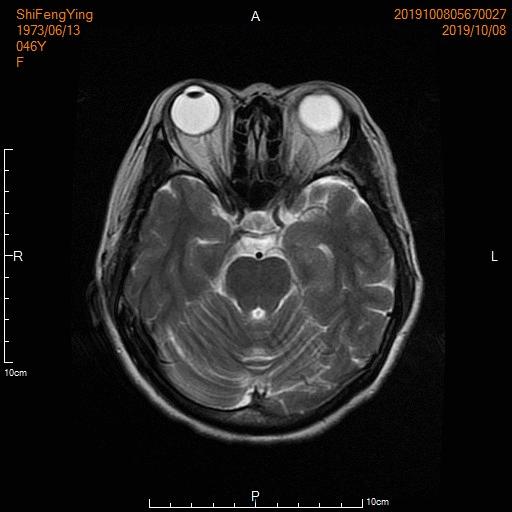

例4:右肺不典型类癌(G2)并多发脑转移

中年女性,头晕、头痛伴肢体乏力1月余。肿瘤标志物不同程度升高。

颅脑MRI显示多发颅脑转移